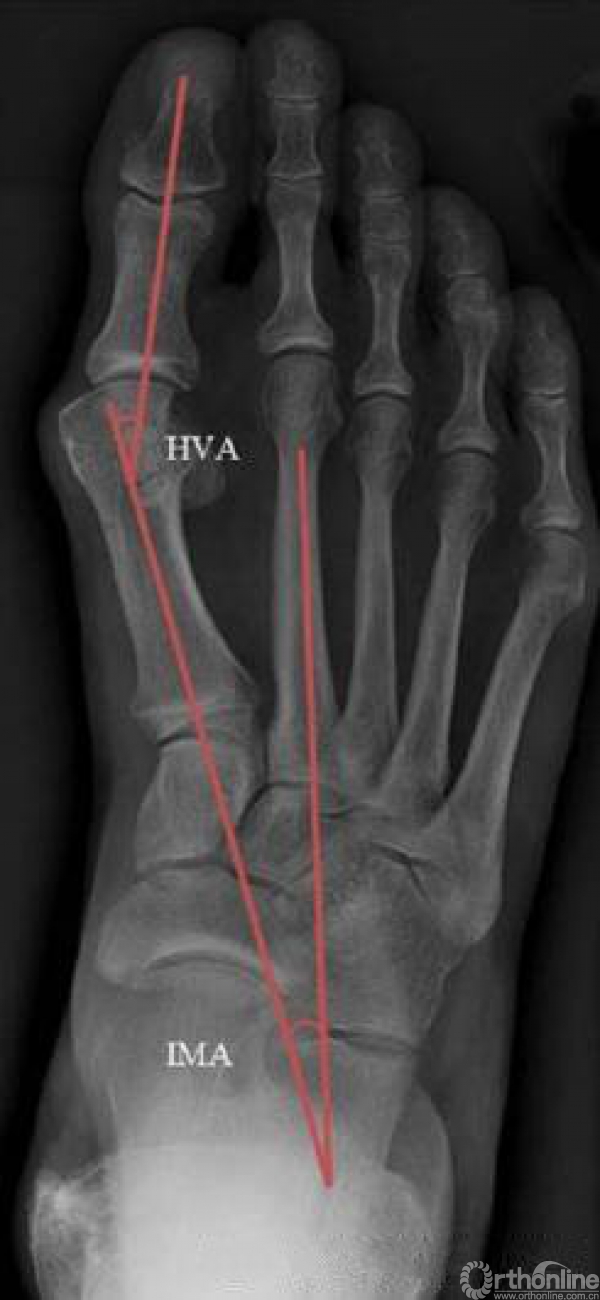

Methods: In this retrospective study, 169 patients who underwent distal chevron osteotomy with or without DWSR were reviewed. Preoperative and postoperative (6 weeks, 6months, 12 months) weightbearing radiographs were evaluated. Functional hallux valgus angle (HVA), intermetatarsal angle (IMA), and the position of the tibial sesamoid were graded using the center of head method. Seventy-six radiographs were available for review at the 12-month follow-up. Of these, 41 patients underwent DWSR procedure and 35 did not.

Results: In both groups, correction of all 3 parameters (HVA, IMA, tibial sesamoid position) were significant at the 12-month follow-up. Comparison of the postoperative results of the 2 groups showed no statistically significant differences. Four feet demonstrated displaced sesamoid position at the12-month follow-up, with radiographic evidence of recurrence in just one. No significant relationship was found between postoperative sesamoid position and hallux valgus recurrence that occurred in 4 feet.

图1. 术前负重正位片上标记拇外翻角(HVA)和跖骨间角(IMA)